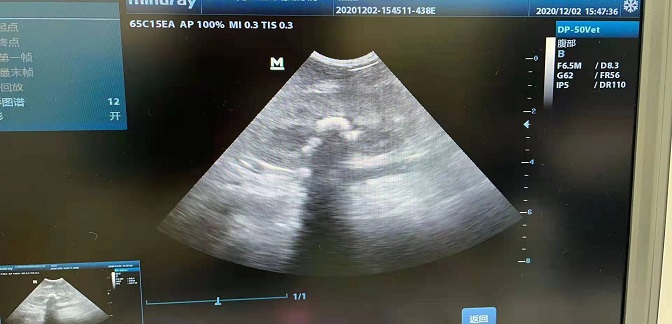

第二天 | ① 犬猫生殖系统和泌尿系统详实器官与结构解剖; ② 生殖系统和泌尿系统各器官正常超声图像 | ① 隐睾超声位置扫查影像; ② 前列腺病变超声扫查影像; ③ 妊娠(心率)超声影像; ④ 子宫蓄脓、积液、捻转与卵巢病变超声诊断; ⑤ 水肾、多囊肾等肾病变超声扫查诊断; ⑥ 膀胱炎症、结石、肿瘤、破裂等超声诊断 | 生殖系统和泌尿系统器官及其病变扫查,每人反复操作。 |

第三天 | ① 消化道胃肠(贲门、胃体、十二指肠、空肠、回肠、盲肠、结肠)超声影像; ② 肝胆与门脉短路检查; ③ 胰腺超声影像; ④ 淋巴结、脾脏、甲状腺、甲状旁腺等超声影像。 | ① 胃肠道、肝脏、胰脏大小器官、结构超声扫查; ② 肝胆常见病的超声诊断扫查; ③ 胰腺病变超声诊断扫查; ④ 隔疝超声诊断扫查; ⑤ 胃淋巴结、肝淋巴结、十二指肠淋巴结等超声扫查 ⑥ 脾脏病变超声诊断; ⑦ 甲状腺病变超声诊断。 |